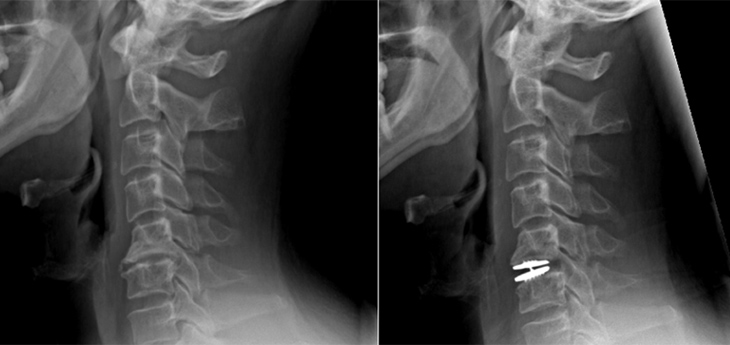

“Mark had disabling headaches with neck and left arm pain. Most physicians don’t connect chronic headache with neck problems,” said Kim, professor of neurological surgery and the chief of spinal neurosurgery. He is also the co-director of UC Davis Spine Center. “Mark needed an anterior C5-6 discectomy to take the pressure off the pinched spinal cord and nerves.”

The most common procedure at that time, called anterior cervical discectomy and fusion, involved removing the damaged disc and fusing the vertebrae to stabilize the spine. But Kim did something more innovative.

“Instead of fusing the spine, Dr. Kim used a device he refined that allows motion. It gave Mark his life back,” Betsy said.

Mark had his operation in September 2014.

The procedure was a lifesaver. “The day after surgery, I had feeling back in my arm for the first time in years. My migraines dropped from 27 a month to three in the first year. It was like I was 20 years younger,” Mark said with a smile.